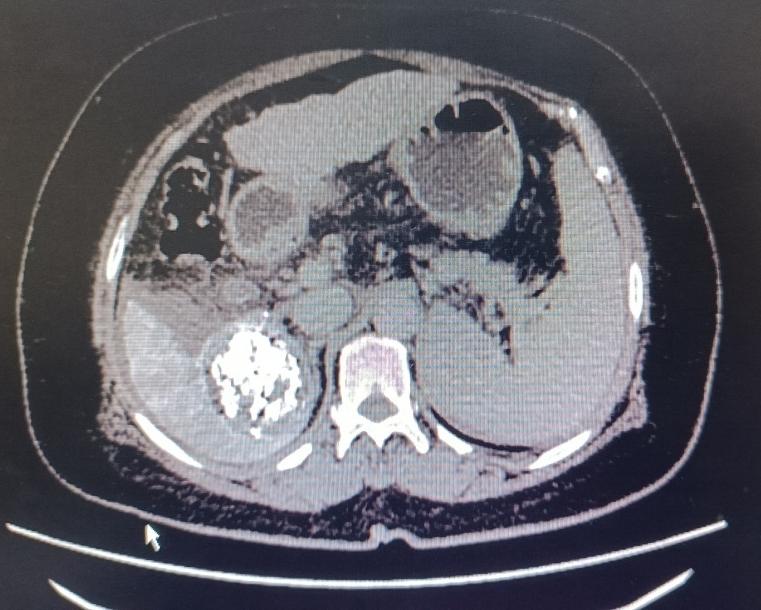

患者女性,57岁,3月12日,突发腹部疼痛就诊于当地医院,CT示肝肿瘤破裂出血,随即转入市中心医院急诊科,分诊后入住普外科二病区。急查实验室检查示:血红蛋白71g/L,血压85/60mmHg左右,正值周日,值班人员电话紧急请介入科会诊,经分析,患者随时有失血性休克风险,当即立断启动疫情状态下的急危重症患者介入诊疗绿色通道。应急值班人员第一时间到位,行肝动脉造影明确了出血动脉(部位),现场评估并制定了手术方案,对肿瘤出血进行了封堵及TACE,术后给予止血、保肝、输血、抗感染等对症处理,病情稳步好转。复查CT肝内碘油沉积良好(提示介入治疗疗效佳),目前已安全出院。